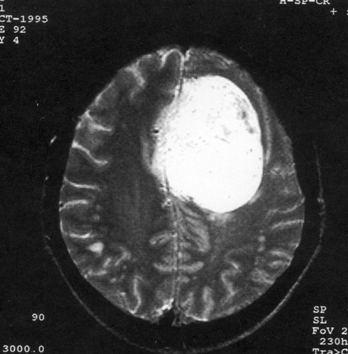

问题 病历摘要:??患者,男,40岁。发作性左下肢抽搐1年余,每次发作3~5分,每周发作1~2次。每次发作后感左下肢乏力,约半日后可自行恢复。既往身体健康。体检:神清,头顶部偏右有局限性骨性隆起(1.5×1.5cm),左鼻唇沟稍浅,伸舌居中。感觉、运动无明显异常。左浅反射减退,左下肢腱反射稍亢进,左Babinski征(-)。 根据病史、MR结果,考虑哪种诊断?提示:头颅?MR检查(见图)

选项 A.右顶叶星形细胞瘤 B.右顶叶转移瘤 C.脑膜瘤 D.右顶叶淋巴瘤 E.右顶叶少枝胶质细胞瘤 F.脑脓肿 G.右顶叶炎性肉芽肿

答案 C